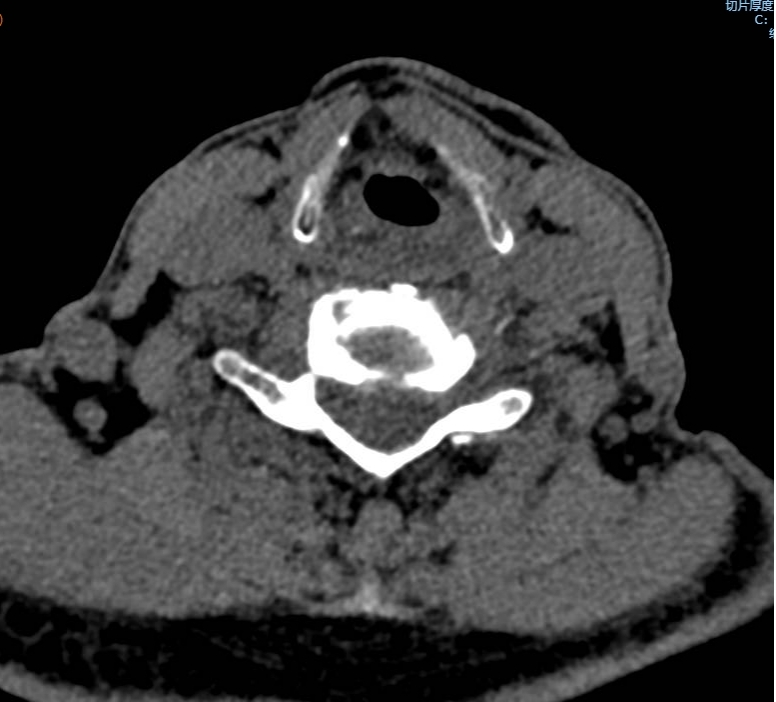

手術(shù)之后3天,黃大伯疼痛得到很好緩解,露出了許久沒有的笑容,終于可以安心躺著睡覺了,1個月后基本恢復了正常生活,6個月后復查CT發(fā)現(xiàn)突出的頸椎間盤已經(jīng)基本消失了,黃大伯一家人對治療效果非常滿意。

手術(shù)之前CT,巨大突出物 術(shù)后6個月復查CT:突出物消失